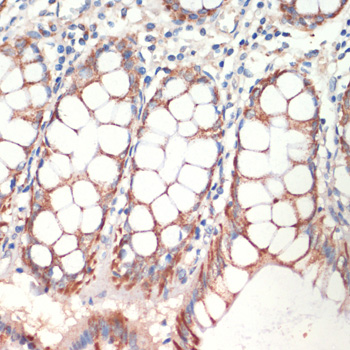

DescriptionAFG3L2 Polyclonal Antibody. Unconjugated. Raised in: Rabbit.

SpecificityHuman, Mouse, Rat

ApplicationWB, IHC, IP